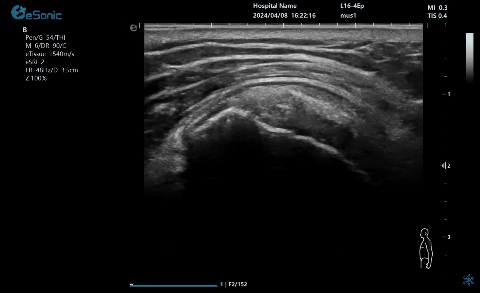

穿刺针智能MAP技术在钙化性肌腱炎的应用

【背景】:冈上肌腱内见强回声钙化灶(见标识箭头)

【治疗】:穿刺捣碎钙化灶,并抽吸;注射药物,消炎止痛。

【痛点】:普通穿刺增强,不能有效区分同为强回声的针尖和钙化灶,医生凭借经验穿刺到钙化灶。

【方案】:穿刺针智能MAP技术,采用智能彩色叠加,避免针与钙化灶混叠而难以区分,帮助引导针尖  精准到达并抽吸钙化灶。